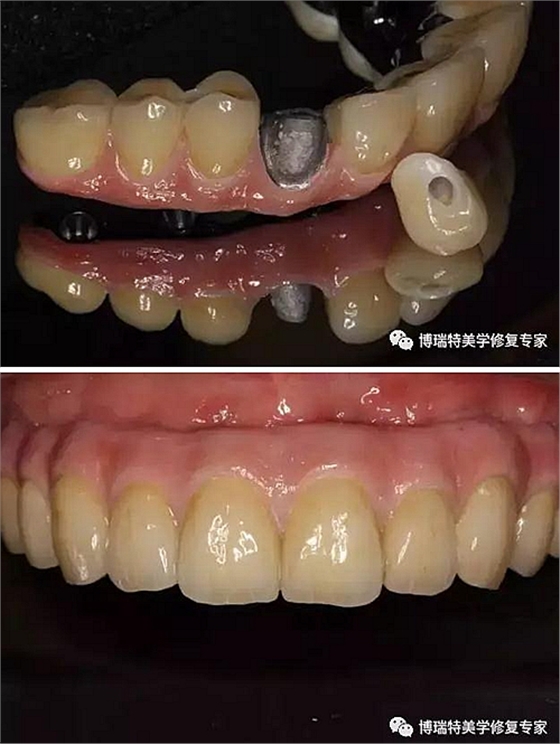

使用螺絲固位基臺手柄安裝螺絲固位基臺,先直基臺后角度基臺;直基臺通過手柄安放,使用工具盒中的球形基臺螺絲刀旋緊至25Ncm;角度基臺通過手柄選擇合適的角度(手柄和直基臺盡量保持平行),然后通過六角螺絲刀安裝中央螺絲,旋緊到25Ncm;

安裝臨時(shí)基臺;

口內(nèi)在臨時(shí)基臺上固定臨時(shí)義齒;

取下臨時(shí)基臺和臨時(shí)義齒口外調(diào)磨修整;

患者口內(nèi)安裝臨時(shí)義齒,完成即刻修復(fù);